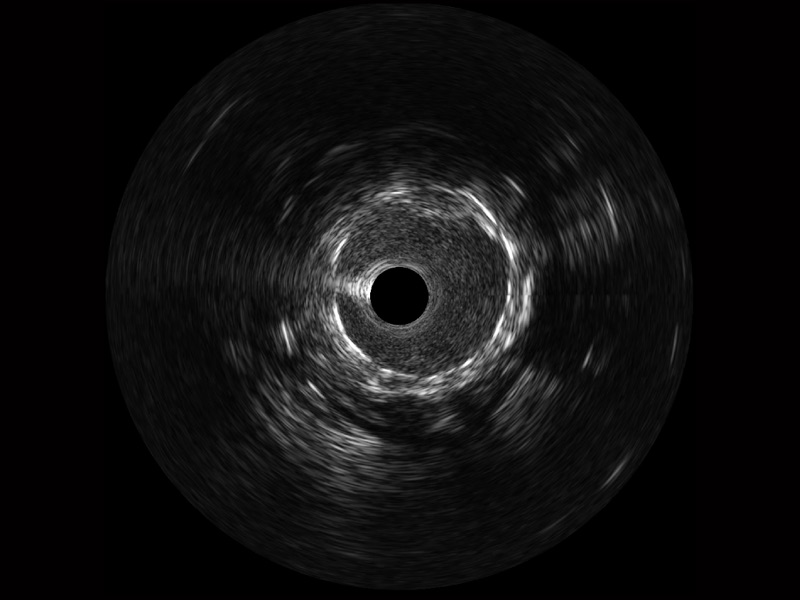

诸侯快讯官网宽频IVUS图像

传统IVUS图像

对比传统IVUS导管成像,诸侯快讯官网宽频IVUS图像的近场支架梁显影更细腻,远场中膜外血管仍清晰可辨,兼顾远中近,兼顾分辨力与穿透深度